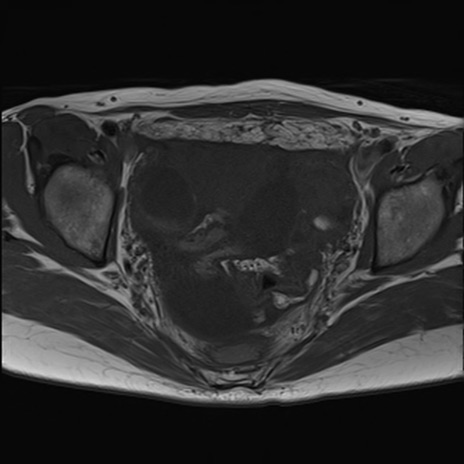

症例39 T1WI(横断像)

MRI(4日後)